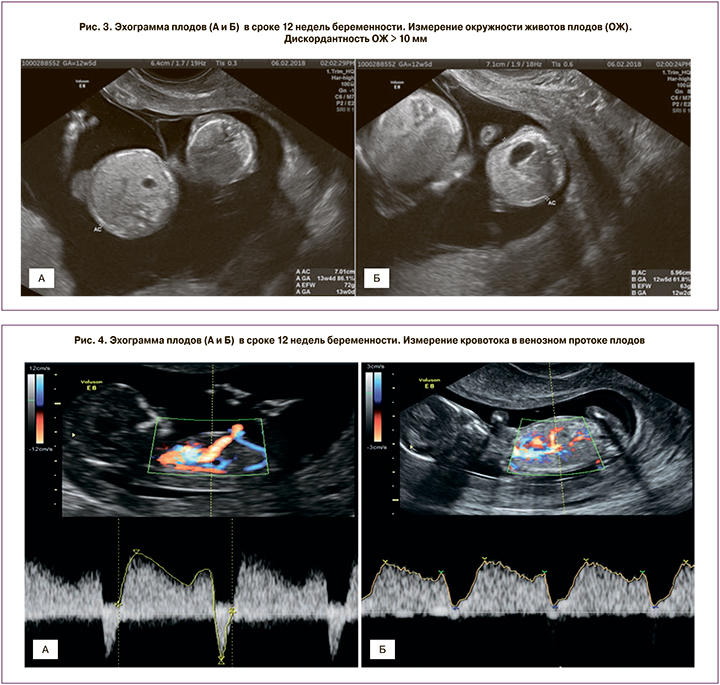

По данным ряда исследований, для прогнозирования развития специфических осложнений монохориальной беременности могут быть использованы такие эхографические параметры I триместра, как толщина воротникового пространства (ТВП) [2, 3], копчико-теменной размер (КТР) плодов [4], характер кровотока в венозном протоке [5]. Ранними проявлениями гемодинамического дисбаланса, развивающегося при ФФТС, могут быть увеличение ТВП одного плода более 95-го перцентиля и/или его дискордантность между близнецами более 0,6 мм, а также изменение кровотока в венозном протоке у одного из плодов [6]. Дискордантность КТР и окружности живота (ОЖ) плодов может являться ранним признаком ССЗРП. Несмотря на то что увеличение ТВП одного из плодов, разница в ТВП и КТР между плодами и аномальный кровоток в венозном протоке показали себя в качестве ранних признаков гемодинамического дисбаланса, возникающего при ФФТС, опубликованные данные неоднозначны. Разница ТВП плодов имеет удовлетворительную чувствительность и специфичность в прогнозировании тяжелых случаев ФФТС, однако такой скрининг до сих пор связан со значительными ложноположительными и ложноотрицательными результатами, так как частота обнаружения составляет всего 52% [7]. Также в качестве предикторов ФФТС предлагались и другие эхографические маркеры, такие как дискордантность по количеству амниотической жидкости [8], обнаружение артерио-артериальных анастомозов [9], складка межплодовой перегородки [10] и изменение уровня циркулирующей материнской м-РНК [11]. Однако их прогностическая значимость не была доказана. Таким образом, в настоящее время остается актуальным поиск ранних диагностических предикторов осложнений монохориальной беременности.

Срок беременности рассчитывался на основании КТР большего плода, измеренного в 11–14 недель беременности. Дискордантность КТР плодов выражалась в процентах и определялась по следующей формуле – разница между плодами, деленная на КТР большего плода. Значимой дискордантность считалась в случае, если она превышала 10%. Измерение ТВП плодов, кровотока в венозном протоке и других параметров скрининга I триместра проводили в сроке беременности 11–13 недель 6 дней согласно рекомендациям Международного общества ультразвуковой диагностики в акушерстве и гинекологии (ISUOG) или Фонда медицины плода (FMF). Сравнительная характеристика различных показателей эхографического исследования в I триместре беременности представлена на рис. 1–4.

При изучении роли дискордантности КТР и ОЖ плодов в качестве предиктора осложнений монохориальной многоплодной беременности было установлено статистически значимое увеличение значений данного маркера в группе ССЗРП (рис. 8).

Данные маркеры оказались прогностически значимыми в отношении развития ССЗРП: для дискордантности КТР площадь под кривой составила 71%, чувствительность – 58%, специфичность – 89% при пороге отсечки 5,5 мм; для дискордантности ОЖ площадь под кривой составила 73%, чувствительность – 73%, специфичность – 74% при пороге отсечки 5,5 мм (рис. 9).

При изучении кровотока в венозном протоке было установлено, что при нормальном течении беременности монохориальной двойней и развитии ССЗРП данный маркер не превышает 95-го перцентиля. Увеличение ПИ кровотока в венозном протоке выше нормативных значений было выявлено в группах с ФФТС и антенатальной гибелью плодов. Тем не менее прогностического значения данного показателя в отношении развития ФФТС, ССЗРП или неразвивающейся беременности выявлено не было.

Ранним предиктором ФФТС, помимо увеличения и/или дискордантности ТВП, является патологический кровоток в венозном протоке. Венозный проток является важнейшим шунтом плода, регулирующим поступление и распределение кислорода и питательных веществ. Изучение кровотока в венозном протоке является одним из наиболее эффективных методов оценки гемодинамики плода. Хорошо изучена роль изменения кровотока в венозном протоке в I триместре беременности в качестве маркера хромосомных аномалий и пороков сердца плода [14, 15]. В основе этих изменений лежит дисфункция сердечно-сосудистой системы. Как было указано выше, ФФТС является результатом гемодинамического дисбаланса, для которого также характерно нарушение работы сердца. У пациентов с ФФТС уже в I триместре беременности диагностируются изменения кровотока в венозном протоке. Патологические изменения в венозном протоке проявляются повышением ПИ более 95-го перцентиля, наличием «нулевого» или «реверсного» типа кровотока [16]. В 11–14 недель беременности существует уникальное состояние гемодинамики и функции сердца, объясняемое законом Франка–Старлинга. Несмотря на то что клиническая картина ФФТС развивается не раньше 16 недель, ранние признаки декомпенсации сердечной функции проявляются уже в 12 недель беременности [17]. При этом в более поздние сроки изменения кровотока в венозном протоке возникают только при III–IV стадиях ФФТС. Данное исследование подтверждает значимость изменения кровотока в венозном протоке в качестве предиктора развития ФФТС. Выявление аномального кровотока в венозном протоке в качестве единственного маркера повышает риск развития ФФТС в 15 раз. При наличии двух маркеров – дискордантности ТВП у плодов ≥0,6 мм и аномального кровотока в венозном протоке риск развития ФФТС увеличивается в 21 раз.

Таким образом, использование комбинации маркеров I триместра – аномального кровотока в венозном протоке и изменений ТВП повышает прогностическую значимость данных параметров. В ходе данного исследования было установлено, что увеличение ТВП более 95-го перцентиля и аномальный кровоток в венозном протоке также являются ранними маркерами антенатальной гибели плодов. Вероятно, антенатальная гибель плодов во II триместре беременности при отсутствии признаков ФФТС возникает вследствие острой гемотрансфузии от одного плода к другому, подтверждением этого являются описанные выше маркеры, которые отражают гемодинамический дисбаланс.